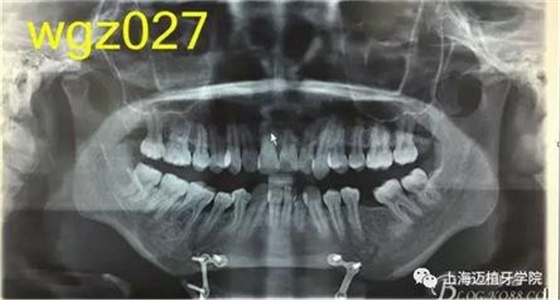

根據(jù)以下上傳的圖片及X線影像資料,你認為她的牙齒存在什么問題?應(yīng)該如何進行矯治設(shè)計?

上海萬眾醫(yī)院正畸科進修醫(yī)生魏倩倩作業(yè)。 某女,25歲。 主訴:頦部術(shù)后自覺牙齒不齊,牙齒凸要求矯正。 既往史:曾有顳下頜關(guān)節(jié)疼痛史,于外院診斷為關(guān)節(jié)不可復(fù)性前移位伴髁突不對稱,行關(guān)節(jié)盤復(fù)位術(shù)。約3個月前在外院行頦成形術(shù),現(xiàn)因牙齒不齊,牙齒凸前來就診。 口外檢查:正面觀,長面型,左右基本對稱,面下1/3過長,頦部明顯水腫,質(zhì)硬; 側(cè)面觀,面型稍凸。 顳合關(guān)節(jié)檢查:無壓痛,左側(cè)彈響,兩側(cè)髁突運動基本一致。 口內(nèi)檢查:恒牙列,下頜前庭處縫合,傷口愈合良好??谇恍l(wèi)生情況一般,牙齦紅腫,LR2、LL6缺失,UR456舌傾與LR67成反合關(guān)系,UR3頰側(cè)突出移位,UR2UL2近中扭轉(zhuǎn),UL1近中外翻唇傾,UR7UL7頰傾,LR6近中傾斜升高,LR5近中傾斜,LR4頰傾移位,LR3冠舌側(cè)傾斜,LL2近中扭轉(zhuǎn)冠頰傾,LL3舌傾,LL78近中傾斜。 模型分析:上頜前牙段擁擠度9.5mm,下頜前牙段擁擠度9mm,spee左右約3mm, LL5、LL7之間間隙約為5mm。上下中線右偏約1.5mm。全牙比約為80%,前牙比62%。磨牙關(guān)系:右側(cè)近中關(guān)系,UL6與LL7遠中尖對尖。尖牙關(guān)系:右側(cè)遠中關(guān)系,左側(cè)近中關(guān)系。 行為分析:患者已于外院行頦成形術(shù),面型已改善,但患者仍覺得牙齒凸,說明患者非常重視面型問題,對美觀要求高。 頭顱側(cè)位片:面型稍凸,上唇在E線前約1.5mm,下唇在 E前約1mm 。 SNA: 85↑ SNB: 75↓ANB: 10↑ U1-L1: 113.6↓ U1-SN: 107.9 L1-M P: 88 ↓Y軸角:65.8 FH-MP: 37↑ SN -M P: 45↑ 曲面斷層片:28顆恒牙,LL6缺失,牙槽骨均位于釉牙骨質(zhì)界以下,LR6、LL7近中牙槽骨角型吸收,頦部可見成型術(shù)鈦合板。左側(cè)升支較右側(cè)粗。 關(guān)節(jié)片:左右髁突不對稱,髁狀間隙右側(cè)明顯較左側(cè)寬,右側(cè)間隙清楚,大小勻稱 ,左側(cè)欠佳。 診斷:安氏3類 骨性2類 高角 上下前牙重度擁擠 中線不齊 間隙分析:下頜 , LL5與LL7之間的有5mm間隙,下頜擁擠度為9mm,整平下頜曲線需要約3mm間隙,下頜需要約12mm間隙,減去現(xiàn)有間隙還需要7mm間隙。上頜,擁擠度為9.5mm,擁擠主要集中在前牙段。 支抗分析:患者頦部術(shù)后仍覺面型凸(主要是上頜前突),所以除了要解決擁擠度外還需要內(nèi)收前牙,所以上頜需要強支抗。患者SNB為75,下頜發(fā)育不足,高角,相對低角病例來說,下頜磨牙較易前移。下頜前牙重度擁擠的情況下主張只解除擁擠不宜內(nèi)收(該患者系下頜后縮病例)。患者ANB為10°,本屬于正頜正畸聯(lián)合治療,現(xiàn)患者已做頦部成型術(shù),患者面型得到改善,故患者現(xiàn)在主要為解決擁擠,少量內(nèi)收前牙,解決上前牙凸度。